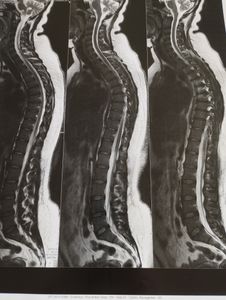

Olá, me chamo Daniele sou uma pessoa alegre e brincalhona, mas ultimamente isso tá ficando difícil, sinto dores frequentes na coluna principalmente na região torácica, isso  tem acabado com minha alto estima, tento sorrir pra pessoas pra disfarçar as dores e me manter forte mas Deus é quem sabe o que tenho passado nesses dois últimos anos.

Gostaria muito da ajuda de vocês pra poder realizar uma Mamoplastia redutora que é a maior causa o peso das mamas, quero estar trabalhando sem sentir dores, voltar a dormir tranquila e fazer atividades simples que hoje em dia me encomenda em executa-las.